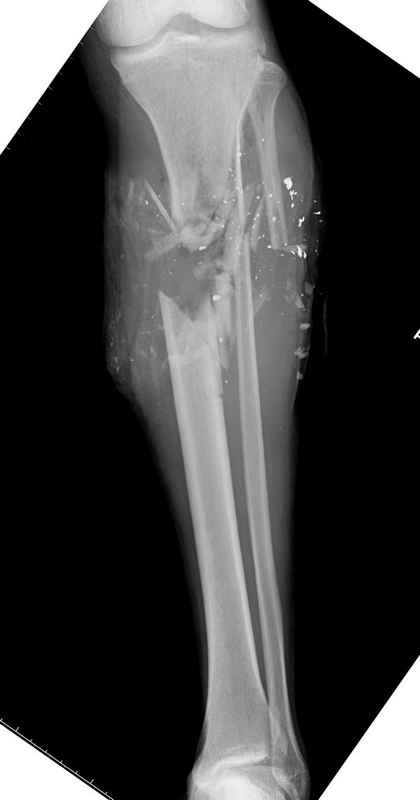

Уважаемые коллеги, Современная тактика лечения огнестрельных переломов вызывает споры. Опыты многих стран доказывает, что открытые переломы можно успешно лечить с применением внутренних металлических конструкций, включая гвозди. В западных странах более 25 лет эту методику применяют для лечения огнестрельных переломов. После применения адекватных методов по предупреждению осложнений, например, после промывания ран, огнестрельные переломы можно стабилизировать без боязни инфицирования. Здесь представлен больной 27 лет с ранениями, включая огнестрельный перелом большеберцовой кости. Стандартный аьгоритм: 11.08.09 доставлен в операционную, Irrigation&Debridment c фиксацией Наружным Фиксатором и вакуумирование VAC; службой травмы пройзведена ангиография с негативным результатом. (снимки 1-10) 14.08.09 повторная Irrigation&Debridment (чувстительственность из раны негативная) со сменой фиксации на медуллярный гвоздь и вакуумирование VAC 18.08 и 21.08.09 Irrigation&Debridment с сменой е VAC, после высеялся MRSA in thio т.е. на специальных срезах небольшое количество (11-13) 25.08.09 повторная Irrigation&Debridment. Пластик хирург не стал рисковать с Soleus flap из-за отечности, и применен Gastric flap, кожная пластика на медиальную и латеральную рану; аллографт из костных стружек с BMP. Поверхность вакуумирована VAC системой на 4 дня (14-16) Финальные снимки сделаем на днях. Djoldas Kuldjanov, MDDepartment of Orthopedic SurgerySt. Louis University Medical Center